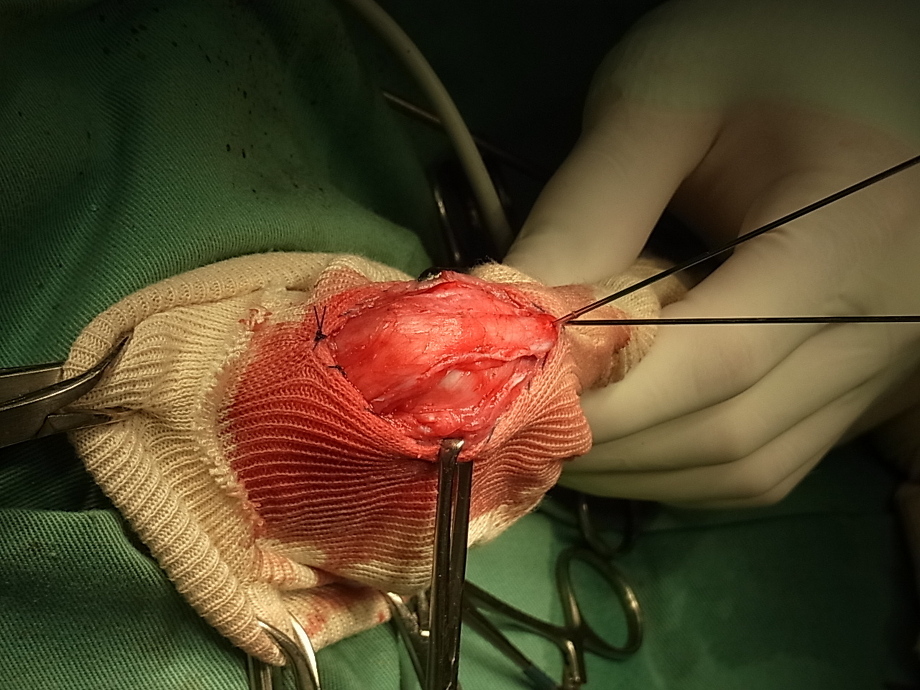

これはヨークシャーテリアの膝蓋骨内方脱臼の手術です。この例もグレード2です。同じようにブロックを切り出しています。

この例では完全にブロックを切り離さずにブロックの下側を削り深くしています。この方法だと切り離していない部分を深くすることができませんので膝の上の方で膝蓋骨が脱臼してしまう場合には注意が必要です。

もどしたところです。キレイに軟骨が温存でき溝も深くなっています。